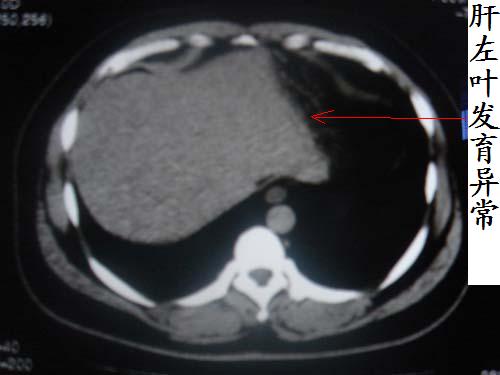

患者 男 40 右上腹不适 有胆囊息肉病史2年

肝脏增大,

片中示肝脏的ct值低于脾脏,肝脏右叶外缘部份凹凸不平,考虑脂肪肝,肝硬化可能。结合其检查如b超或ct增强检查。

胆囊未见明显异常,肝脏密度似比脾脏密度低,测量一下ct值排除一下脂肪肝.当然做一下增强或mr就更好了.

肝右叶密度不均,脾大。强烈要求增强扫描除外浸润型肝癌。

肝大   密度降低  脾大  脂肪肝?